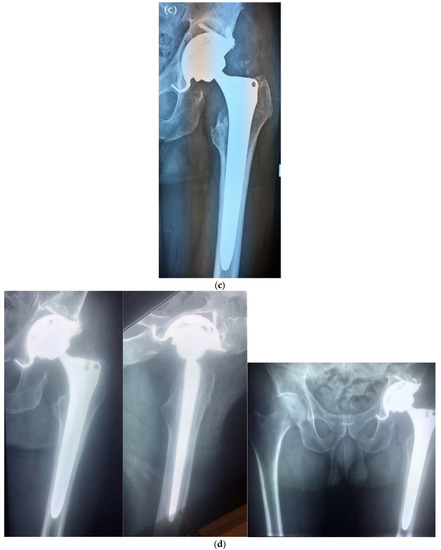

| Hip Joint | 38 (54.3%) |

| Cementless prosthesis implantation | 49 (70%) |